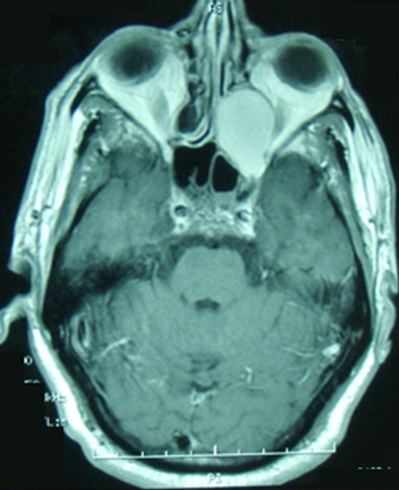

Les mucocèles sont des complications tardives et rares de la radiothérapie. Ils sont le plus souvent de siège ethmoïdal postérieur ou sphénoïdal. Ils peuvent exceptionnellement entrainer des troubles visuels graves par compression du nerf optique. Le diagnostic est évoqué par les données cliniques et de l'imagerie. Le traitement est chirurgical avec un examen histologique systématique afin d'éliminer une récidive tumorale. Patient âgé de 48 ans avait des antécédents d'un cancer du cavum ( UCNT : undifferenciated carcinoma of nasopharyngeal type) classé T2 N1 M0, traité par chimio et radiothérapie, 3 ans auparavant, avec évolution favorable. Il a été hospitalisé pour épistaxis gauche de faible abondance et douleur orbitaire homolatérale évoluant depuis 3 mois. L'examen physique a objectivé un cavum libre, un état général conservé et des aires ganglionnaires libres. La TDM du massif facial a révélé une formation éthmoïdale gauche, ovoïde, de 3 cm de grand axe, qui amincit les parois osseuses et bombe dans le secteur postéro-interne de l'orbite avec un cavum libre. L'IRM du massif facial a trouvé une lésion kystique de 3 cm de grand axe en hypersignal T1 et hypersignal T2, de siège éthmoïdal postérieur, s'étendant au niveau de la paroi interne du massif orbitaire gauche et comprimant le nerf optique homolatéral. Une récidive du cancer du cavum a été suspectée. Le patient a bénéficié d'une marsupialisation par voie endoscopique. L'examen anatomo-pathologique était en faveur d'une mucocèle. L'évolution était favorable avec un recul d'un an.